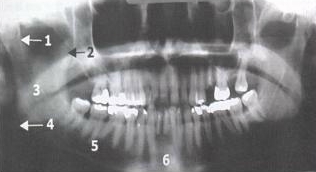

Standard Mandibular Series: Panoramic View

Single Most Useful Film In Diagnosis Of Mandibular Fracture

Fracture of Condylar Process, Ramus, Body Of Mandible